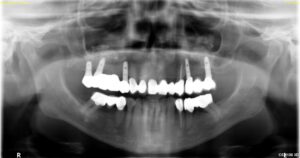

Kontrollröntgenbild nach Bohrung unterhalb der Kieferhöhle mit Messinstrumenten